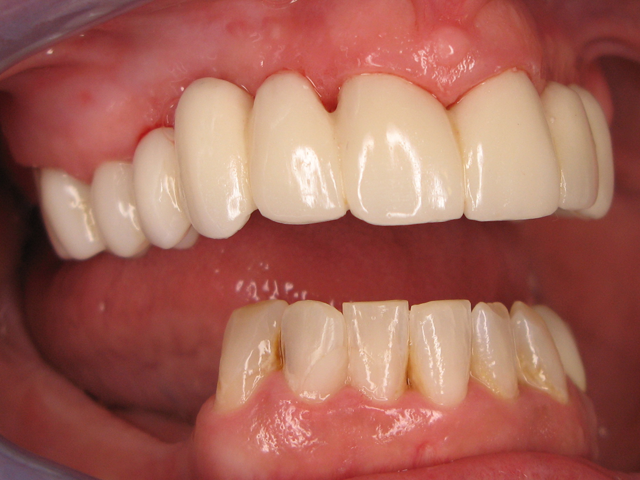

Here is the finished case before sending it back to the dentist (Figs. 23-25) and here is the final seated case (Figs. 26-28).

Fig. 23                                                                            Fig. 24

Fig. 25                                                                   Fig. 26

As you can see from the picture, the patient was extremely happy with her permanent smile and so was the doctor.